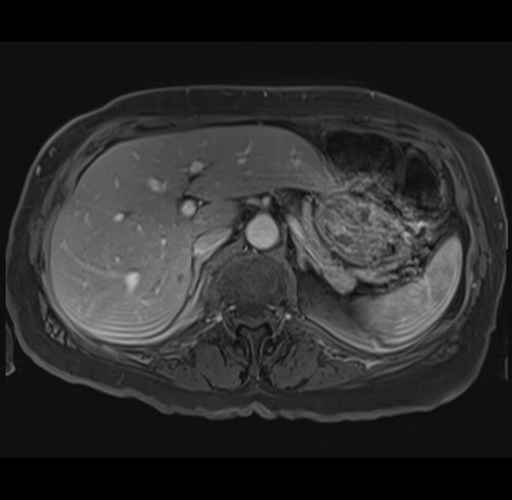

MRI T1